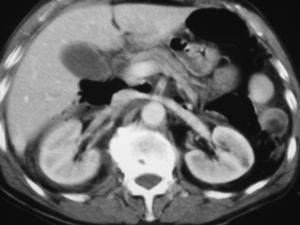

Varón de 73 años, que vive en un ambiente rural, sin alergias medicamentosas conocidas ni antecedentes clínicos de interés. Acude al servicio de urgencias con un dolor abdominal difuso, bastante intenso, tras haber tenido una caída accidental por las escaleras varias horas antes. A la exploración presentó un abdomen ligeramente peritonítico, doloroso, no distendido y sin hematomas visibles. La exploración neurológica, torácica y de las extremidades no reveló alteración alguna. En la analítica sólo destaca leucocitosis (13.500/μl) y el resto es normal. La radiografía abdominal mostró aire extraluminal en la zona superior derecha, y en la tomografía computarizada (TC) se confirma un neumoretroperitoneo (fig. 1), por lo que se procede a realizar una serie gastrointestinal con contraste hidrosoluble oral que demostró la existencia de varios divertículos a nivel de segunda y tercera porciones duodenales, con la extravasación de contraste en uno de ellos (fig. 2).

Fig. 2. Serie gastrointestinal: extravasación de contraste en uno de los divertículos duodenales.